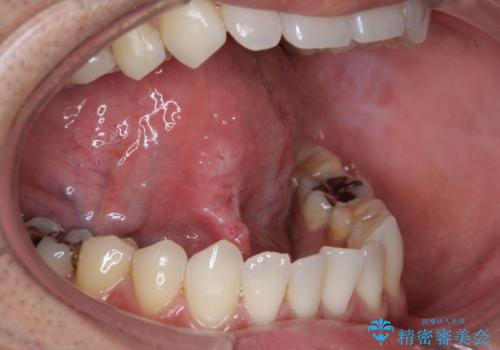

- 舌を動かしにくいとのことで来院されました。

舌の裏側にある舌小帯という部分が短い状態だったため、舌小帯の切除をすることとなりました。

術後の治りも良く、以前よりも話しやすくなったと大変喜んでいただけました。